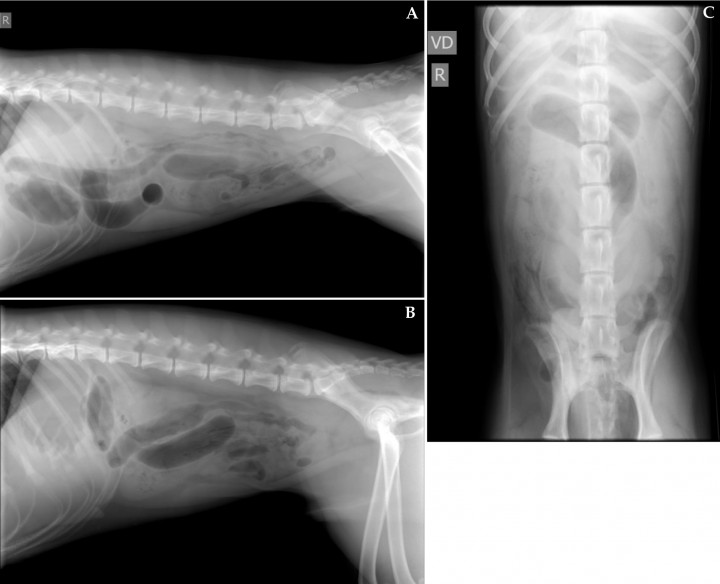

Acude a consulta un cachorro de 7 meses, macho, mestizo que presentaba episodios de vómitos, anorexia y apatía desde hacía 24 horas. El examen físico fue normal y no se observaron alteraciones relevantes en las analíticas sanguíneas. Se realizaron radiografías lateral derecha (Fig. 1A), izquierda (Fig. 1B) y ventrodorsal (Fig. 1C) de la cavidad abdominal.

<p>Radiografías de abdomen. (<strong>A</strong>) Lateral derecha. (<strong>B</strong>) Lateral izquierda. (<strong>C</strong>) Ventrodorsal.</p>

Radiografías de abdomen. (A) Lateral derecha. (B) Lateral izquierda. (C) Ventrodorsal.

Se visualizan varias asas de intestino delgado dilatadas y apiladas localizadas en abdomen craneal y medio, con contenido de opacidad gas y tejido blando en su interior (Fig. 2) y otras que mantienen su tamaño normal. Una de estas asas, localizada entre abdomen medio-caudal (Figs. 2A y B) y en el lado derecho (Fig. 2C), se encuentra dilatada con un ratio de diámetro del asa respecto a altura del cuerpo de la vértebra L5 de 2,8 (ratio normal 1), con un contenido de opacidad tejido blando y presencia de gas dispuesto en un patrón de líneas radiolúcidas y moteado. Este contenido se extiende a lo largo del asa desde la cuarta vértebra lumbar hasta el sacro.

<p>Mismas radiografías que la Figura 1. Se observan varias asas de intestino delgado dilatadas y apiladas localizadas en abdomen craneal y medio, con contenido de opacidad gas y tejido blando en su interior (flechas negras). En abdomen medio-caudal (<strong>A</strong> y <strong>B</strong>) y en el lado derecho (<strong>C</strong>), se visualiza otra asa dilatada con un ratio de diámetro del asa respecto a altura del cuerpo de la vértebra L5 de 2,8, con un contenido de opacidad tejido blando y presencia de gas dispuesto en un patrón de líneas radiolúcidas y moteado (flechas blancas).</p>

Mismas radiografías que la Figura 1. Se observan varias asas de intestino delgado dilatadas y apiladas localizadas en abdomen craneal y medio, con contenido de opacidad gas y tejido blando en su interior (flechas negras). En abdomen medio-caudal (A y B) y en el lado derecho (C), se visualiza otra asa dilatada con un ratio de diámetro del asa respecto a altura del cuerpo de la vértebra L5 de 2,8, con un contenido de opacidad tejido blando y presencia de gas dispuesto en un patrón de líneas radiolúcidas y moteado (flechas blancas).